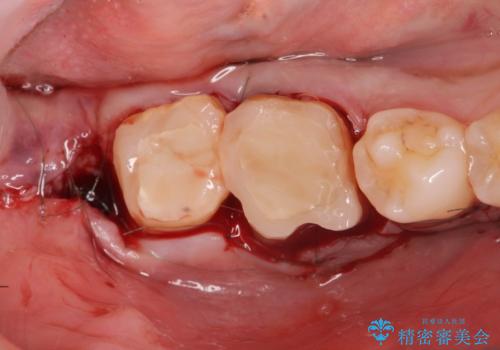

金属のクラウンは薄く加工しても壊れないことがメリットですが、セラミッククラウンを装着するにはスペースが少なすぎ、このまま治療を進めると外れやすく壊れ易いセラミッククラウンの設計となるため、歯周外科を行い狭小なスペースの拡大を行うこととしました。

なんとかギリギリのスペースを確保するこおtができ、無事銀歯を外してセラミック治療を行うことができました。